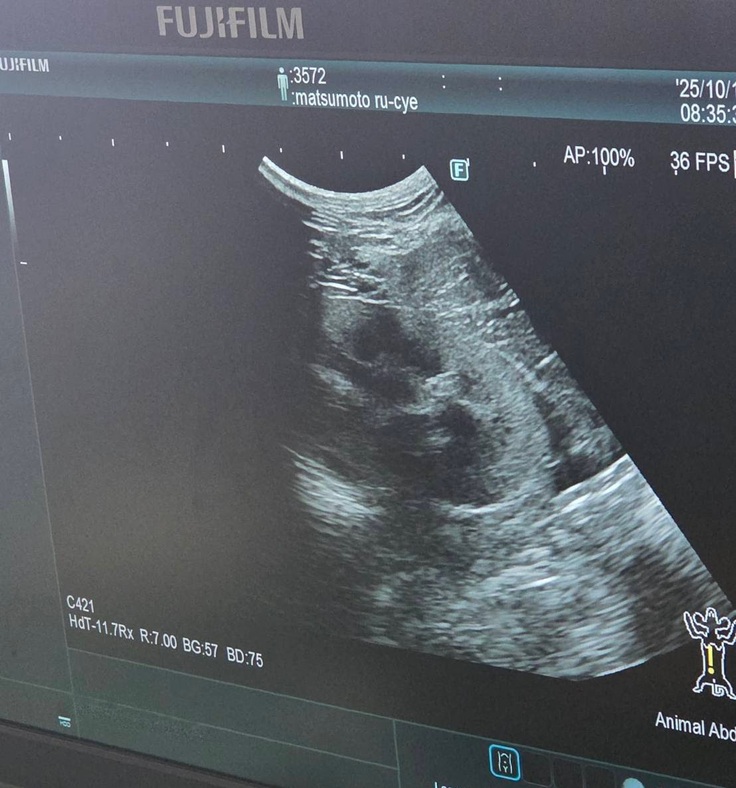

血液検査の写真は撮れなかったのですが、エコー検査では

↓腎臓転移なし

↓反対側の腎臓も転移なし